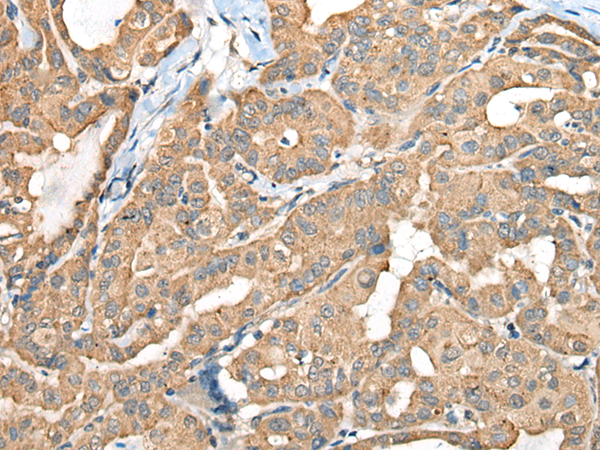

IHC positive control: |

Human thyroid cancer |

IHC Recommend dilution: |

40-200 |